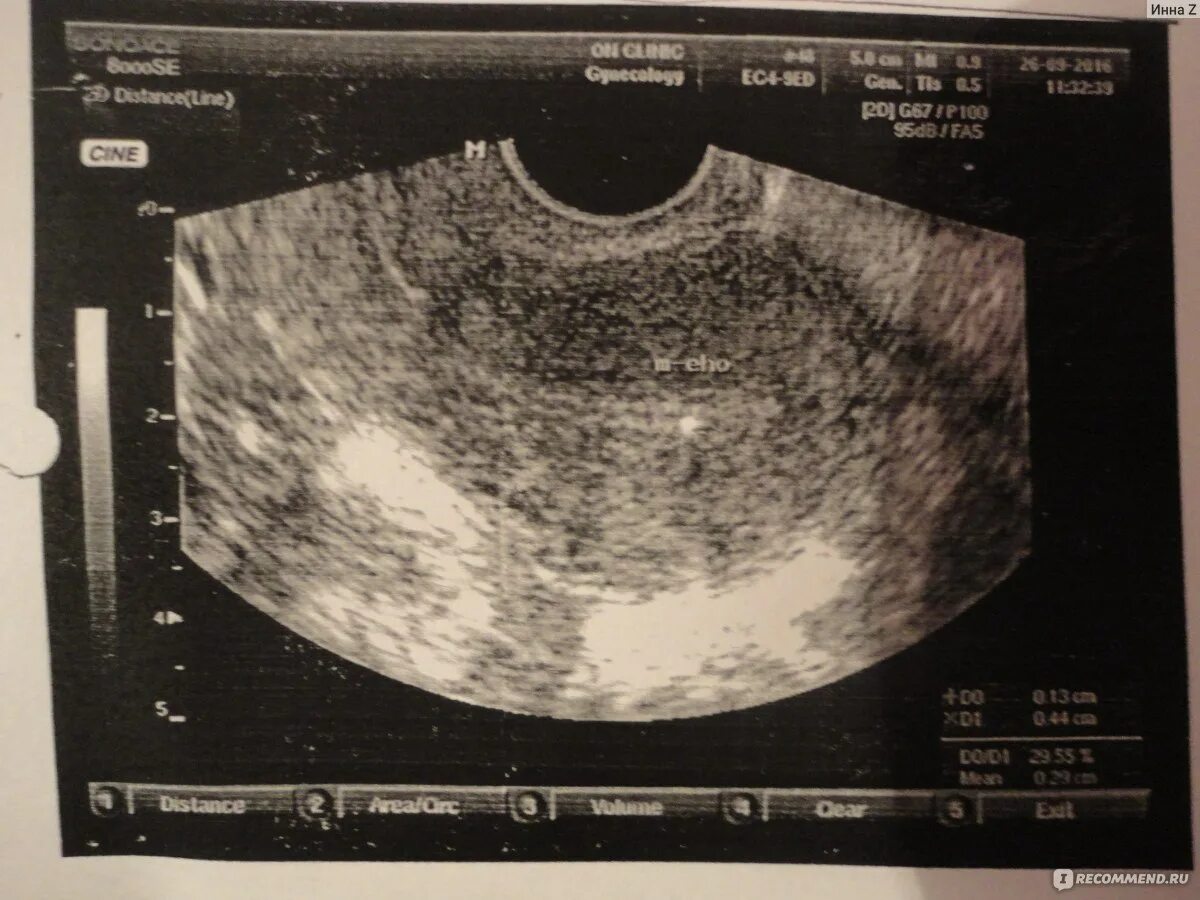

Трансвагинальное узи можно ли девственницам